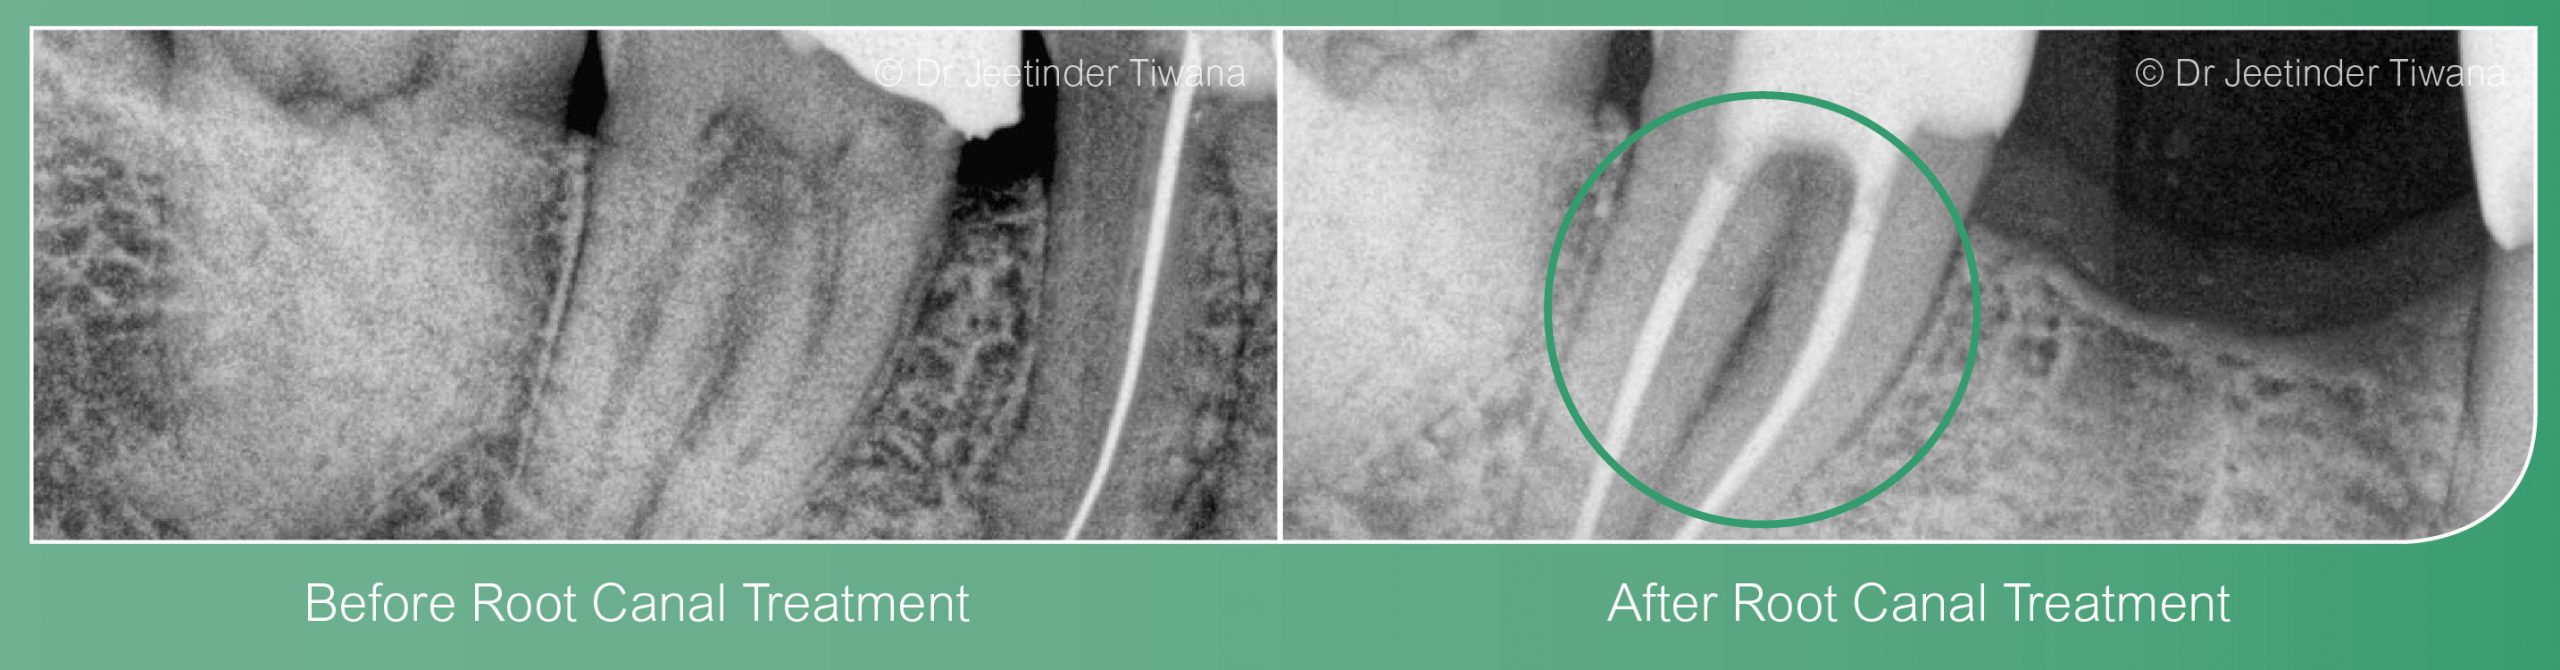

Advanced root canal treatment at Styvechale Dental Care is carried out by Dr Jeetinder Tiwana who has a special interest in Endodontics. Dr Tiwana is a friendly, cheerful person and a caring dentist. He is very passionate about what he does and likes keeping up to date with the latest developments in dentistry.